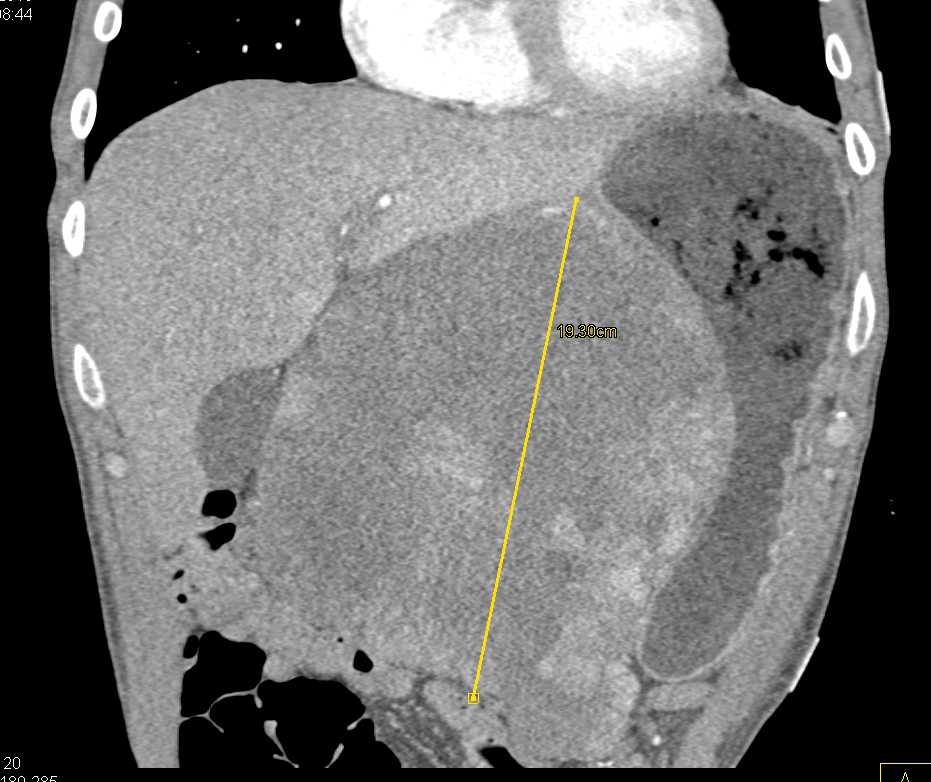

Lagre Gastric GIST Tumor